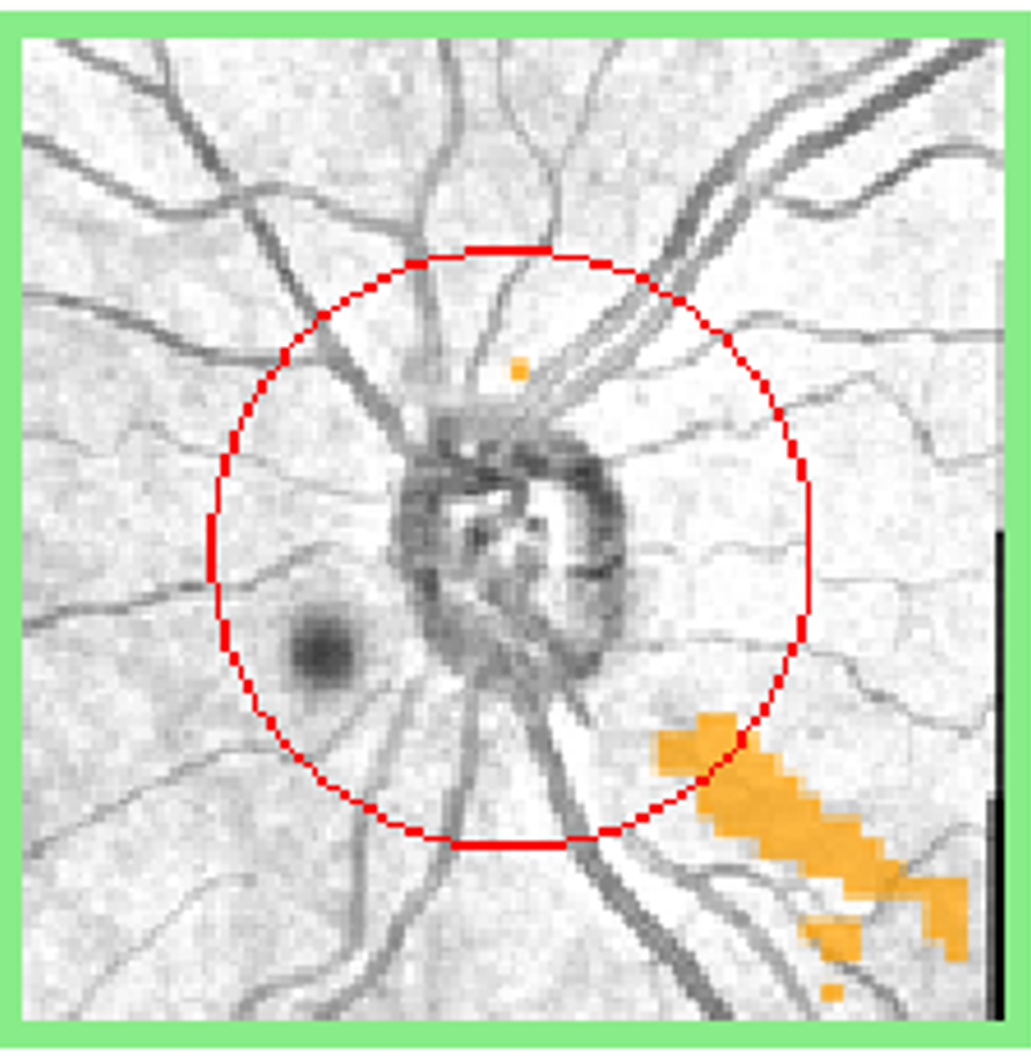

More infoRed-free images at baseline and follow up

Case 2: Disc haemorrhage and functional loss in a patient with glaucoma

A 74 year old Caucasian female with a history of thyroid disease who is being treated with Xalatan for bilateral glaucoma. At baseline, her intraocular pressure (IOP) in the right eye was 17mmHg in the context of average corneal thickness (562µm). At follow-up 6 months later, her IOP was the same.